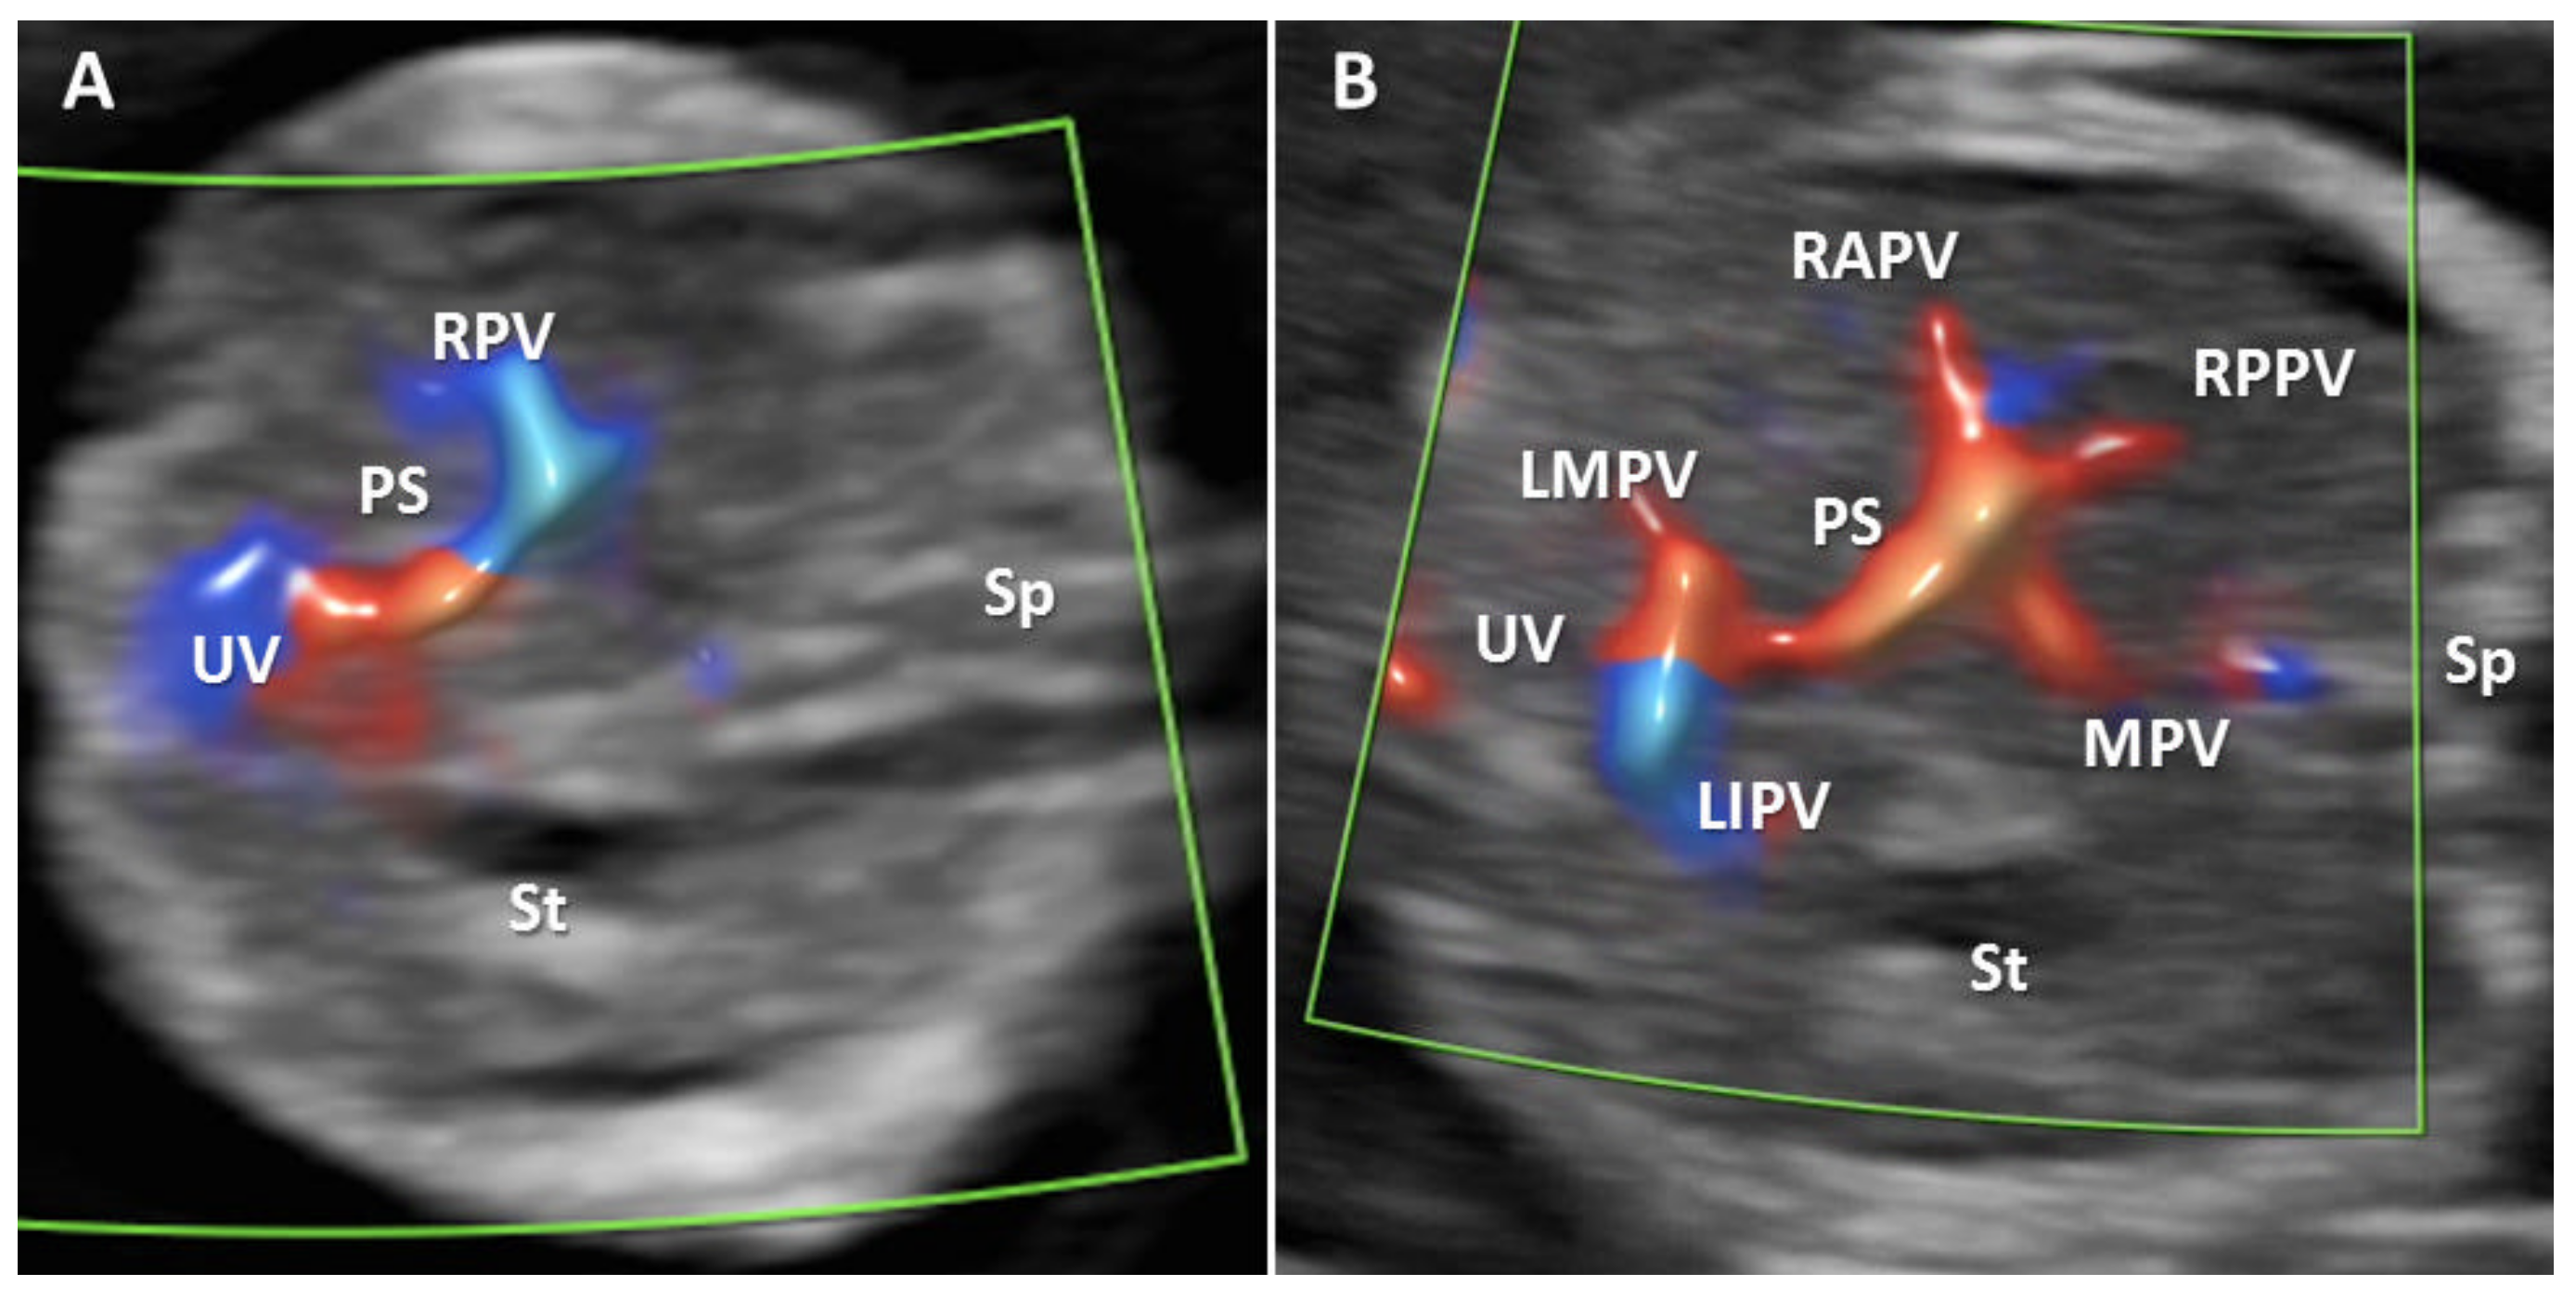

- Mavrides, E.; Moscoso, G.; Carvalho, J.S.; Campbell, S.; Thilaganathan, B. The anatomy of the umbilical, portal and hepatic venous systems in the human fetus at 14-19 weeks of gestation. Ultrasound Obstet. Gynecol. 2001, 18, 598–604. [Google Scholar] [CrossRef] [PubMed]